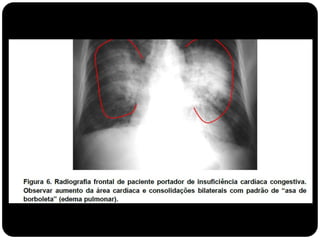

Padrão Alveolar  Opadrão alveolar ou do espaço aéreo é caracterizado por opacidade homogênea.  Ocorre pela ocupação do espaço aéreo por outras substâncias que não o ar: exsudato nas pneumopatias, transudato nos edemas pulmonares, sangue, células neoplásicas e materiais estranhos no caso de aspiração (ex. aspiração de óleo mineral)

Conceitos  Atelectasia: ausênciado ar alveolar;  Consolidação: substituição do ar alveolar (não há redução de volume);

 Quando ocorreessa consolidação os brônquios em seu interior podem tornar-se visíveis – broncograma aéreo.